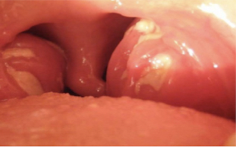

22

Quel est le diagnostic?

Amygdalite aiguë